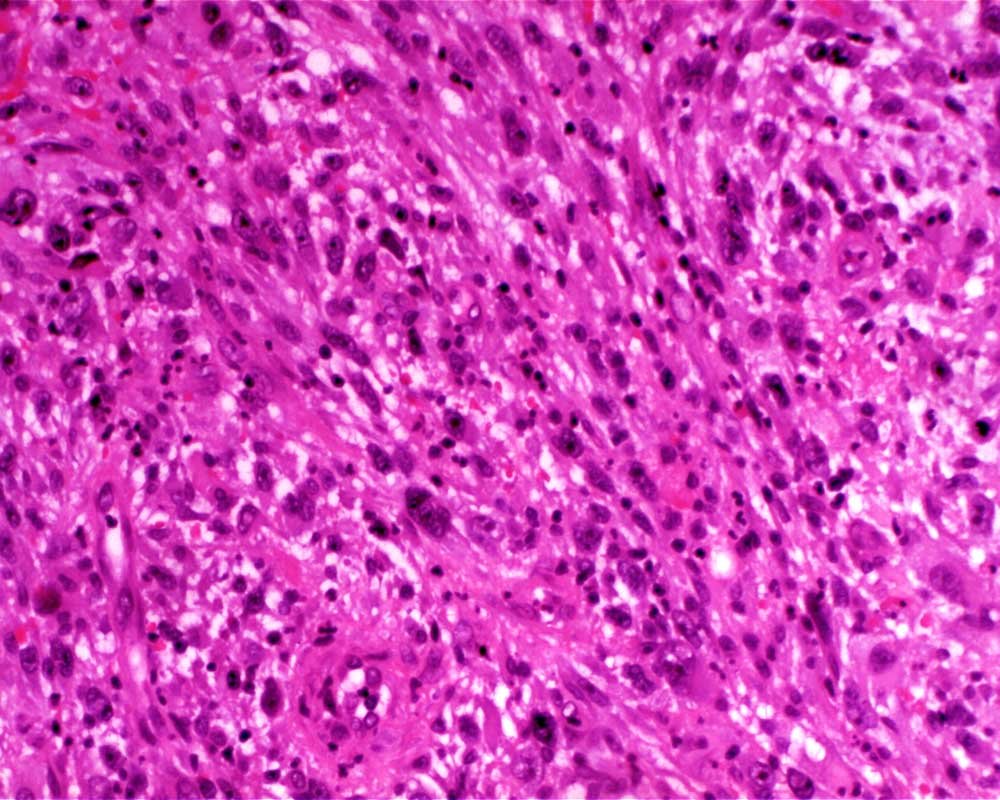

Case: LegMass

Final Diagnosis: